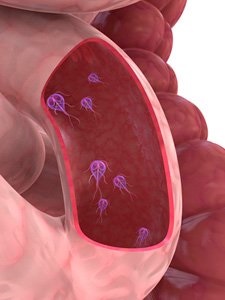

Az orvosi gyakorlatban, Giardia hívják egysejtű ostoros szervezetekre. Ezek a paraziták, amelyek osztják 2 formák, ami az ilyen betegségek például a giardiasisnak. Az első forma - ez trophozoiták él a felső része a vékonybél, a második ciszták. Giardia ciszták formában megszerzett bevétele a vastagbélbe, majd ürül a test mellett egy székre, miközben a megélhetés.